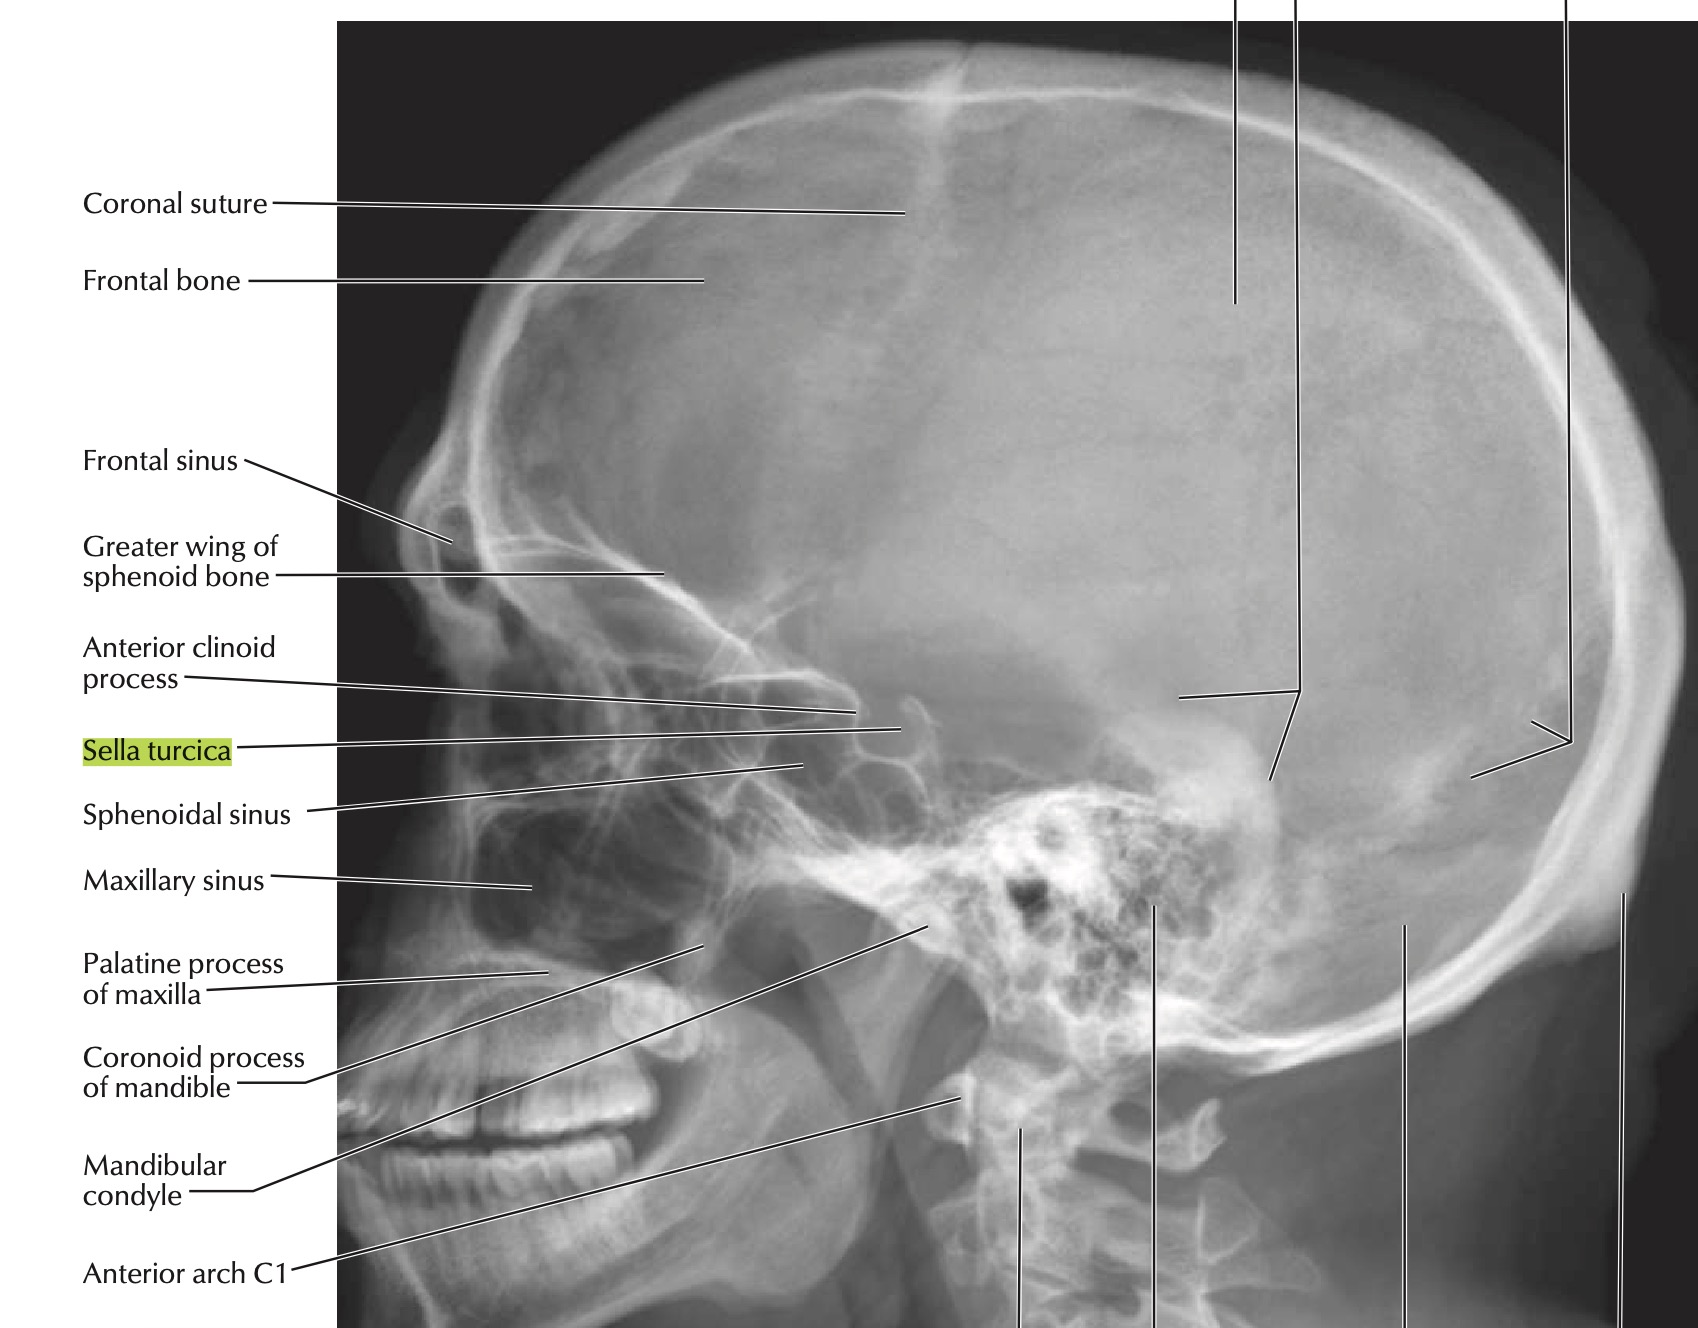

sits in the body of the sphenoid in the sella turcica